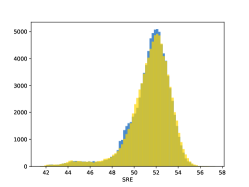

To visualise similarity metrics that compare image pairs (RMSE, SRE, SSIM) two metric distributions are generated: intra-similarity and inter-similarity. For each compared sample 300 random images are selected. The inter-similarity distribution is calculated for each image pair combination from both compared samples e.g. generated images of COVID-19 and real images of COVID-19. For the intra-similarity, all pairs of images in a single sample e.g real images of COVID-19 are considered. By comparing the shape of intra-similarity for the training subsample (Dataset) with the inter-similarity of training and generated samples the quality of the generated sample can be judged. It is also possible to compare in this way between the four image classes present in the dataset. The resulting distributions of inter-similarity of COVID-19 and the three remaining classes are compared in Fig. 4 to distributions of intra-similarity of the COVID-19 sample for each metric. All metrics, as expected based on available medical evidence Rubin et al. (2020), indicate that there are visible differences not only between COVID-19 and normal samples but also between viral pneumonia and lung opacity. Therefore, all classes should be distinguishable.

To visualise differences between synthetic and real samples distributions are generated for each of the RMSE, SRE and SSIM metrics: intra-similarity and inter-similarity. For each compared sample 300 random images are selected. The inter-similarity distribution is calculated for each image pair combination from both compared samples e.g. generated images of COVID-19 and real images of COVID-19. For the intra-similarity, all pairs of images in a single sample e.g real images of COVID-19 are considered. The distributions for generated samples describe very well the distributions for corresponding real images as shown in Fig. 6.

The quality of generated images is also confirmed with classical similarity metrics. The distributions of those similarity measures between generated and real images are compared for each sample with the distribution obtained within the real samples 6. The distributions for generated samples describe very well the distributions for corresponding real images. For an example see the results for the SSIM metric presented in Fig. 10. The small visible differences are almost insignificant compared to differences observed between the classes in Fig. 4.